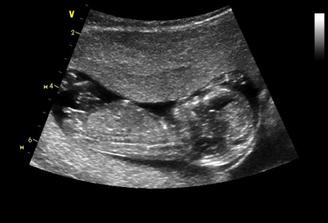

23.6.2009 dle utz 6+4 tt, dvě bušící srdíčka, předběžný termín porodu 15.2.2010,

30.6.2009 dle utz 7+3 tt, stále dvě bušící srdíčka,

14.7.2009 dle utz A 10+0tt, B 9+4tt, u obou aktivní pohyb 🙂termín porodu upřesněn na 11.2.2010, a 4.8.jdu na NT screening -dopadl skvěle, jsme 13+0tt, obě stejně velká, termín 9.2.2010

23.9.velký ultrazvuk